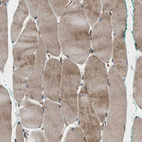

Immunohistochemical staining of human skeletal muscle strong granular cytoplasmic positivity in myocytes.